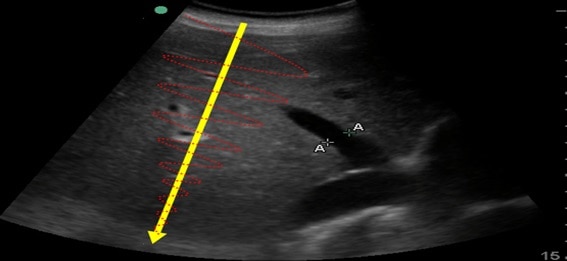

En la imagen siguiente, se puede apreciar el fémur de un paciente. El ultrasonido llega hasta la interfase del hueso (muy denso) con el tejido circundante (muy poco denso) y se refleja con una intensidad alta (y por eso se muestra más “blanco” en la pantalla, como luego veremos).

Sin embargo, si atraviesa una interfase menos definida, en la que las densidades son similares, se dispersará en muchas direcciones diferentes, produciendo un eco de baja intensidad (que se representarán más “grises” en la pantalla), como ocurre al atravesar el parénquima hepático, donde las interfases son de densidad muy similar.